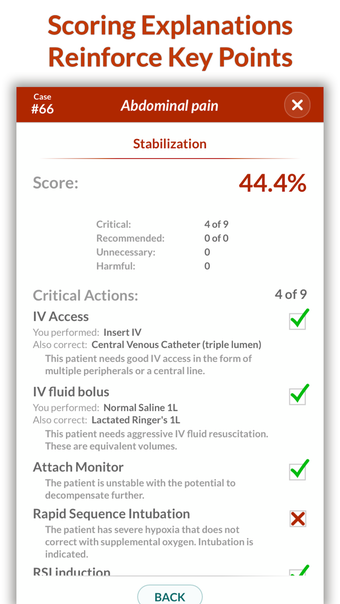

Full Code - Emergency Medicine Simulation è un'applicazione Android sviluppata da Minerva Medical Simulation Inc. È una versione completa con licenza di un'applicazione di stile di vita che rientra nella sottocategoria medica. È un'applicazione di simulazione intuitiva, mobile-first che offre oltre 160 casi virtuali realistici e un'interfaccia coinvolgente simile a un gioco, preferita dai professionisti medici di tutto il mondo. L'applicazione è progettata per aiutare gli studenti e i professionisti medici a acquisire fiducia nel trattamento di casi complessi e offre 0,5 crediti AMA PRA Categoria 1™ per ogni caso Full Code giocato con Full Code Pro+CME.

L'applicazione consente agli utenti di esercitarsi in diagnosi cliniche rare e rischiose in un ambiente sicuro in modo da poter affrontare casi complessi del mondo reale con fiducia. Con oltre 160 casi in 31 specialità, Full Code consente di esercitarsi in simulazioni mediche on-demand ogni volta che si ha una pausa, ovunque ci si trovi. L'applicazione è ottimizzata per la portabilità e l'accessibilità ed è disponibile su qualsiasi dispositivo mobile, desktop o tablet. Full Code è accreditato attraverso l'ACCME e, con la sua sottoscrizione PRO+CME, gli utenti possono completare i loro requisiti di formazione medica continua (CME) con sfide di simulazione flessibili e piacevoli. È un'applicazione eccellente per i professionisti medici che vogliono migliorare le proprie competenze e acquisire fiducia nel gestire casi complessi.